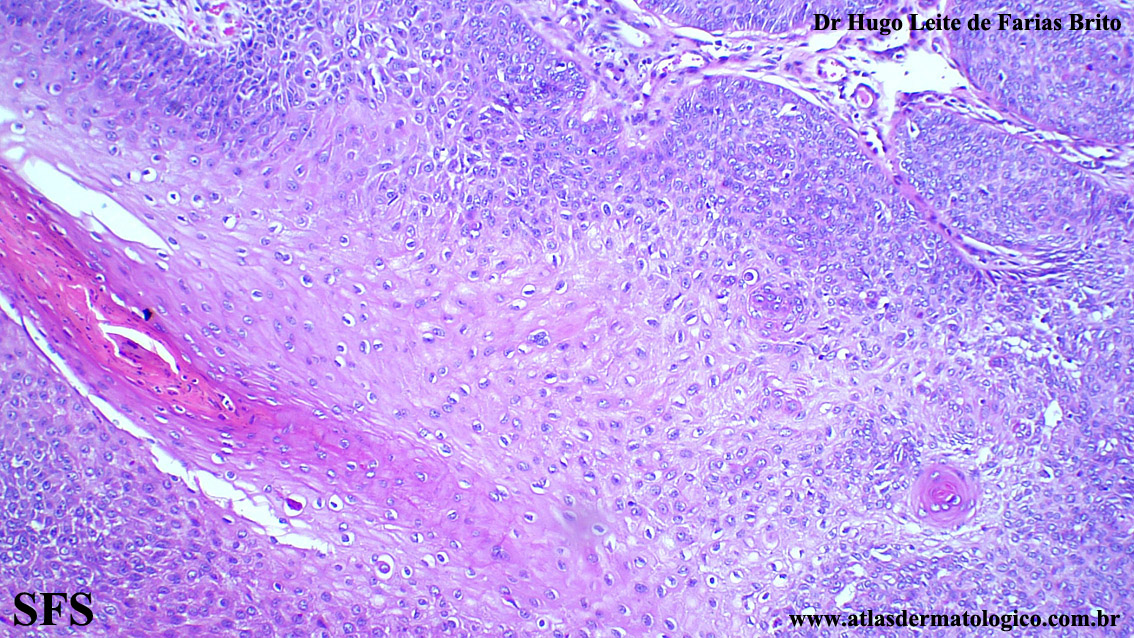

trichilemmoma-desmoplastic_trichilemmoma